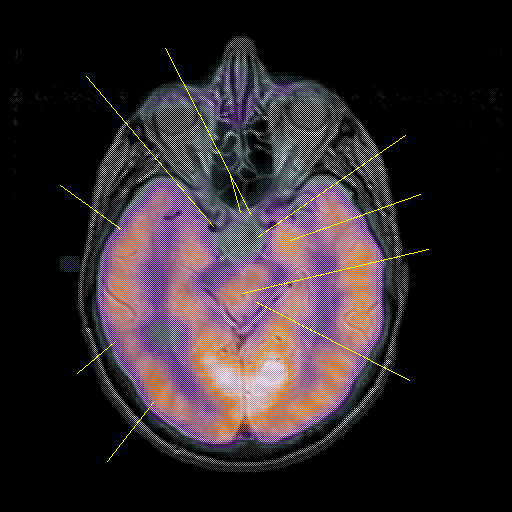

overlay : Slice 23

Slice 23

Unlabeled

Pointers

Labeled